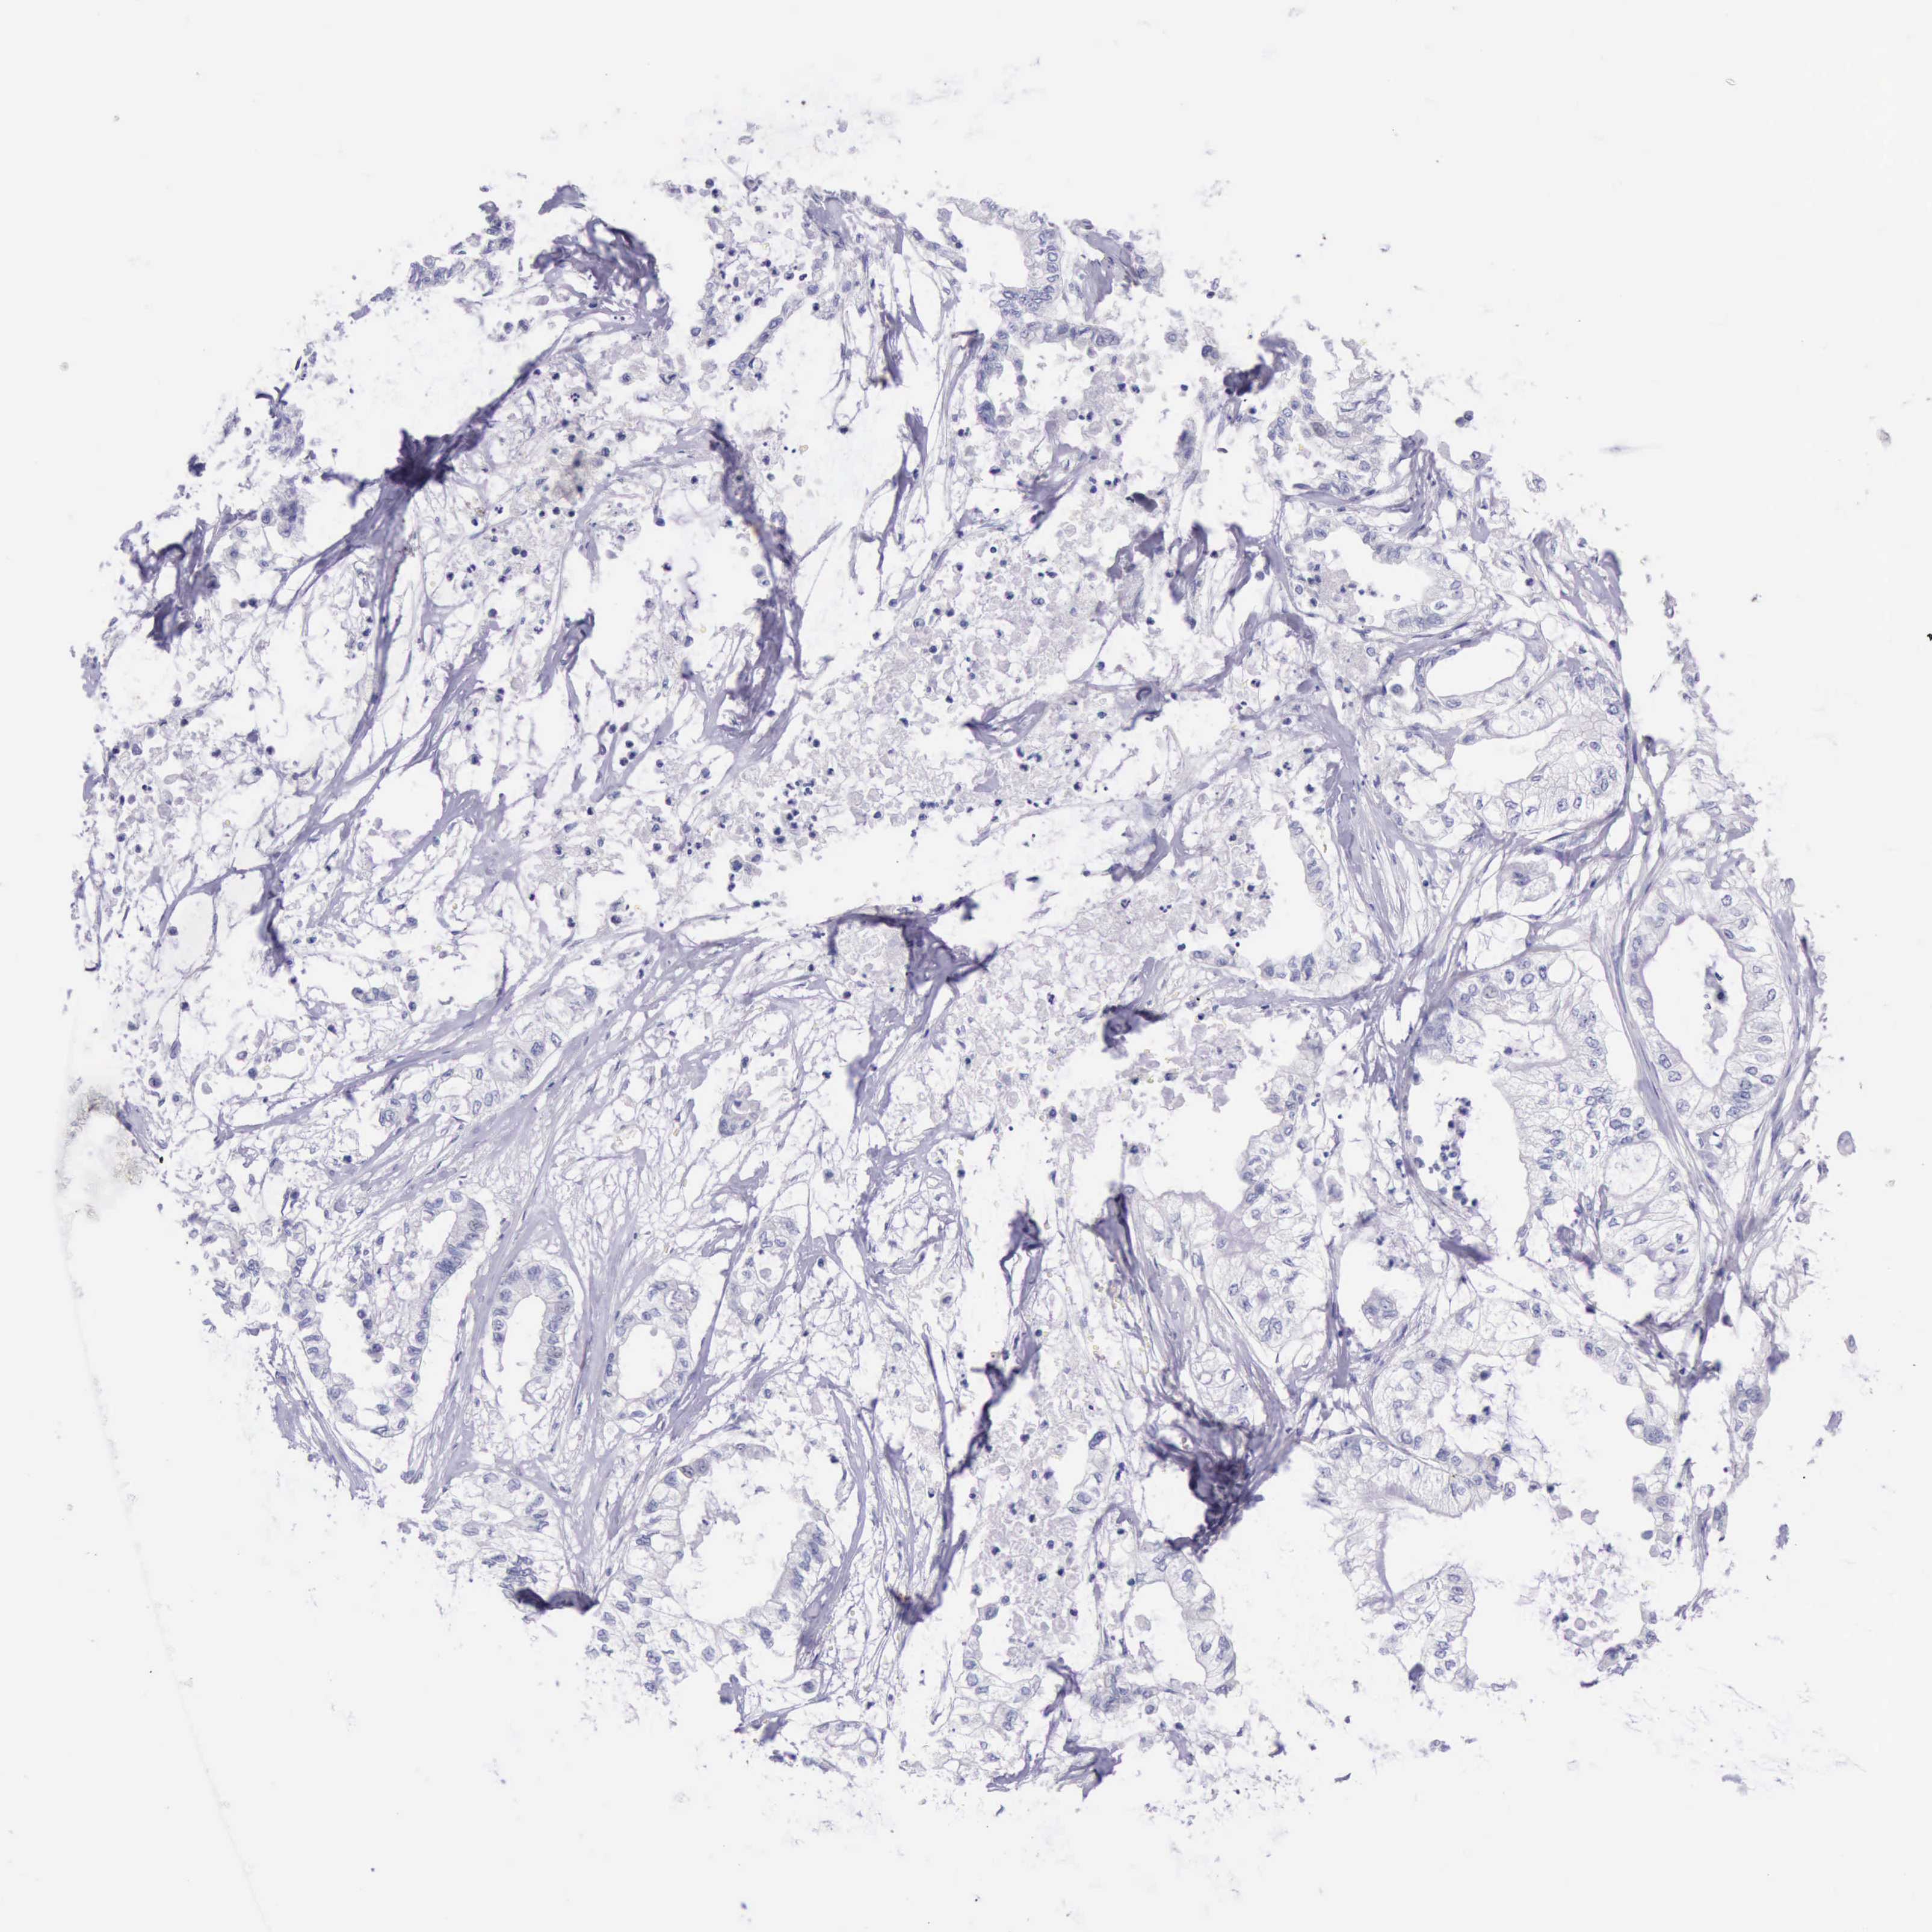

PANCREATIC CANCER - Protein expressioni

A mouse-over function shows sample information and annotation data. Click on an image to view it in a full screen mode. Samples can be filtered based on level of antibody staining by selecting one or several of the following categories: high, medium, low and not detected. The assay and annotation is described here.

Note that samples used for immunohistochemistry by the Human Protein Atlas do not correspond to samples in the TCGA dataset.

Antibody stainingi

Antibody staining in the annotated cell types in the current human tissue is reported as not detected, low, medium, or high, based on conventional immunohistochemistry profiling in selected tissues. This score is based on the combination of the staining intensity and fraction of stained cells.

Each image is clickable and will lead to virtual microscopy that enables deeper exploration of all samples and also displays staining intensity scores, fraction scores and subcellular localization as well as patient and tissue information for each sample.

Antibody HPA001177

Staining

High

Medium

Low

Not detected

Intensity

Strong

Moderate

Weak

Negative

Quantity

>75%

75%-25%

<25%

None

Location

Nuclear

Cytoplasmic/membranous

Cytoplasmic/membranous,nuclear

Adenocarcinoma, NOS